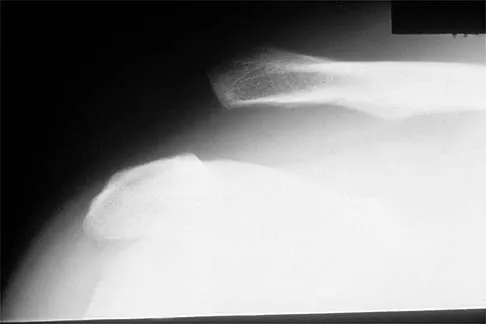

A 30-year-old man has pain in the left arm after a motor vehicle accident. His neurovascular examination is intact, and radiographs are shown in Figures 25a and 25b. What is the best course of management?